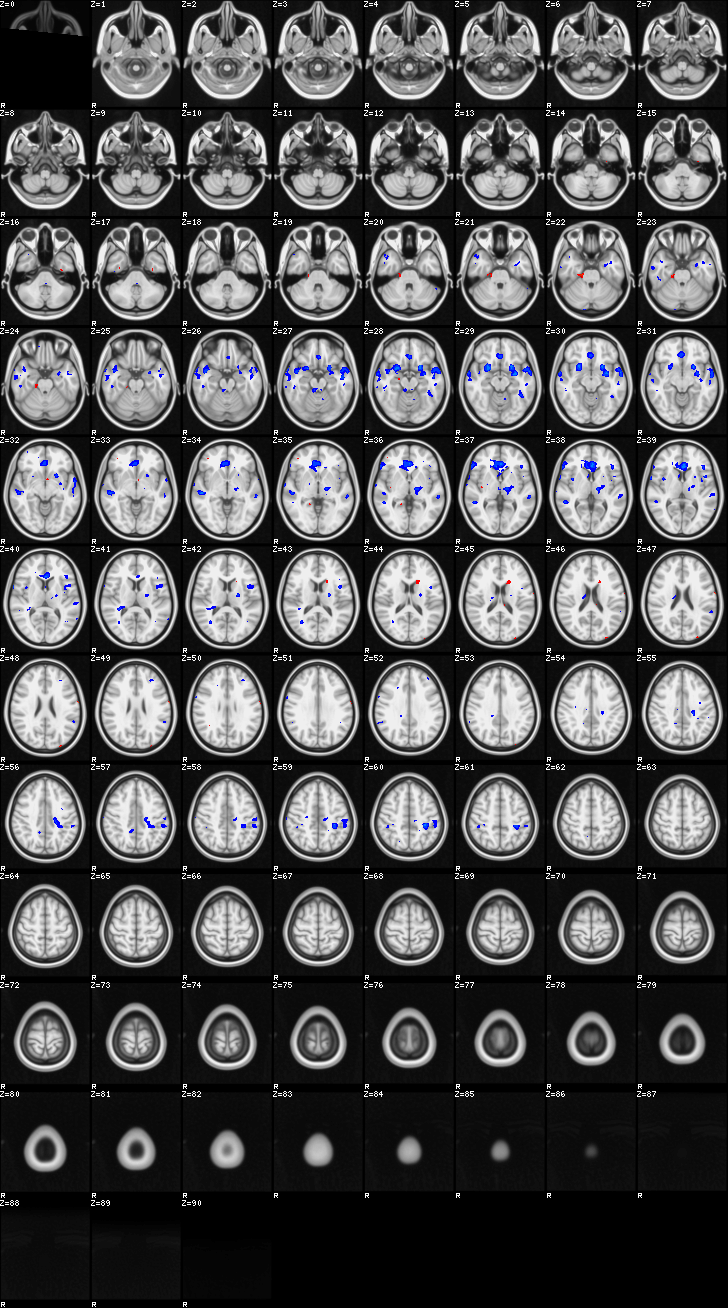

Mixed Effect (flame1)¶

ATM it is 8 subjects, 8 mm FWHM spatial smoothing, preliminary results only

Images thresholded abs value > 2.3 and colormap goes from 2.3 to 5 (red->yellow) or -2.3 to -5 (blue->lightblue)

Contrasts:

- FltC

- Well – the opposite, and since both sides are plotted, it is just inverted colormap

01-FltC¶